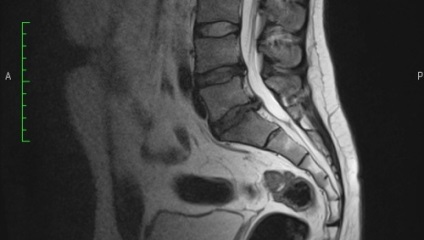

Prolapsul discului intervertebral în nivelul L5-S1

Proeminența din spate pe scanari RMN